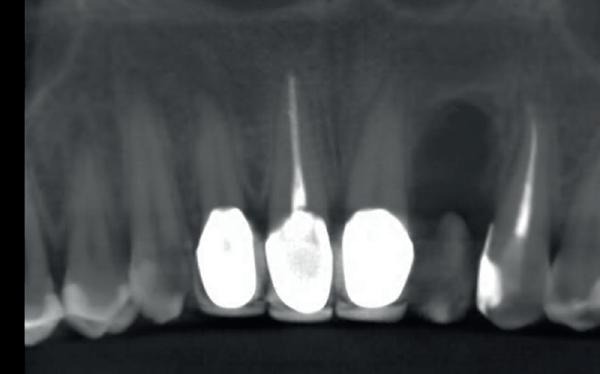

In deze casus is extractie van de 37 geïndiceerd in verband met een fistel en restpockets, zoals zichtbaar op de röntgenfoto’s (afbeelding 1). Duidelijk te zien is de forse peri-apicale ontsteking en het botverlies bij de 37, dat zowel richting buccaal als linguaal doorloopt. De 37 wordt atraumatisch verwijderd. Er is aan de linguale zijde veel bot verloren en er is sprake van een perforatie aan de buccale zijde.

Er wordt besloten om botmateriaal te plaatsen in de extractie-alveole. Vervolgens wordt het afgesloten met een titanium versterkt d-PTFE membraan (afbeelding 2). Na vier weken wordt het membraan verwijderd.

Zes maanden na extractie wordt het implantaat 37 geplaatst. Er is sprake van een goede genezing en de processushoogte en -breedte zijn behouden en opgebouwd. Ook is er zichtbaar gekeratiniseerd weefsel

1 2 Ridge preservation met d-PTFE membranen 35

gewonnen. De wond kan na het plaatsen van een healing abutment primair gesloten worden (Afbeelding 3a-3d).

In afbeeldingen 4a-c is het resultaat drie maanden na het plaatsen van het implantaat te zien. De genezing is volledig en de verwijzer kan de suprastructuur vervaardigen (afbeelding 4a-4c).

In afbeeldingen 5a-d is de implantaatkroon 37 te zien, twee jaar na plaatsing. Op de röntgenfoto is herstel van zowel corticaal als spongieus bot te zien. (De CB-CT was vervaardigd in verband met implantologische indicatie in het naastliggende gebied).